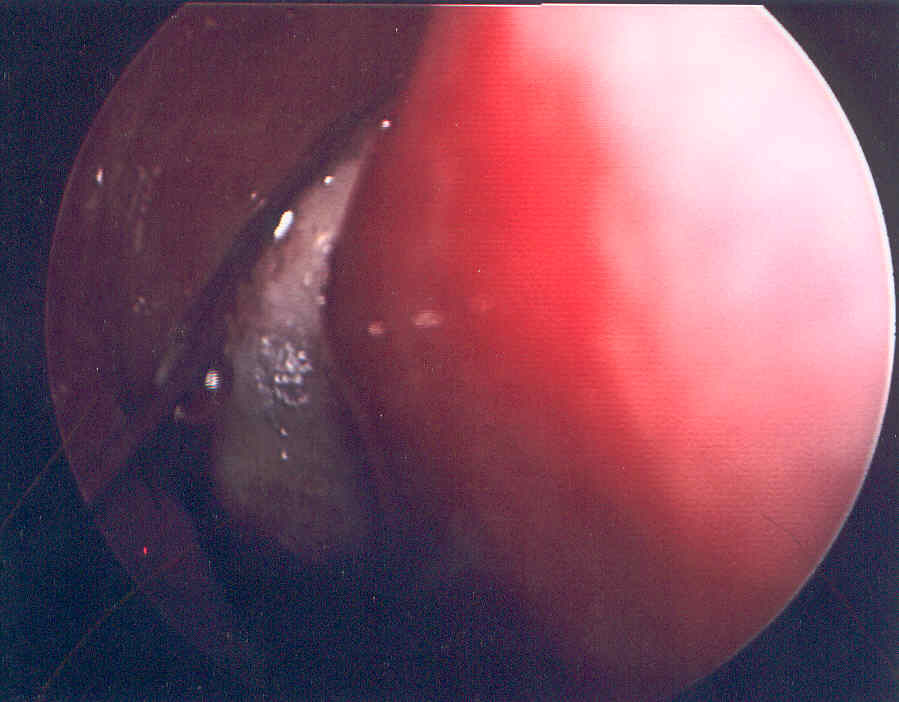

The patient depicted here had a relapse of her Acute myelogeous leukemia.  She complained of facial pain and congestion.  Her sinus CT was not impressive, but her exam was dramatic: her right middle turbinate is seen in the middle.

The turbinate blanches as the fungal organism invades the blood vessels and kills the tissue.

A needle is seen poking the turbinate, and produces no bleeding: a sure sign of tissue necrosis.